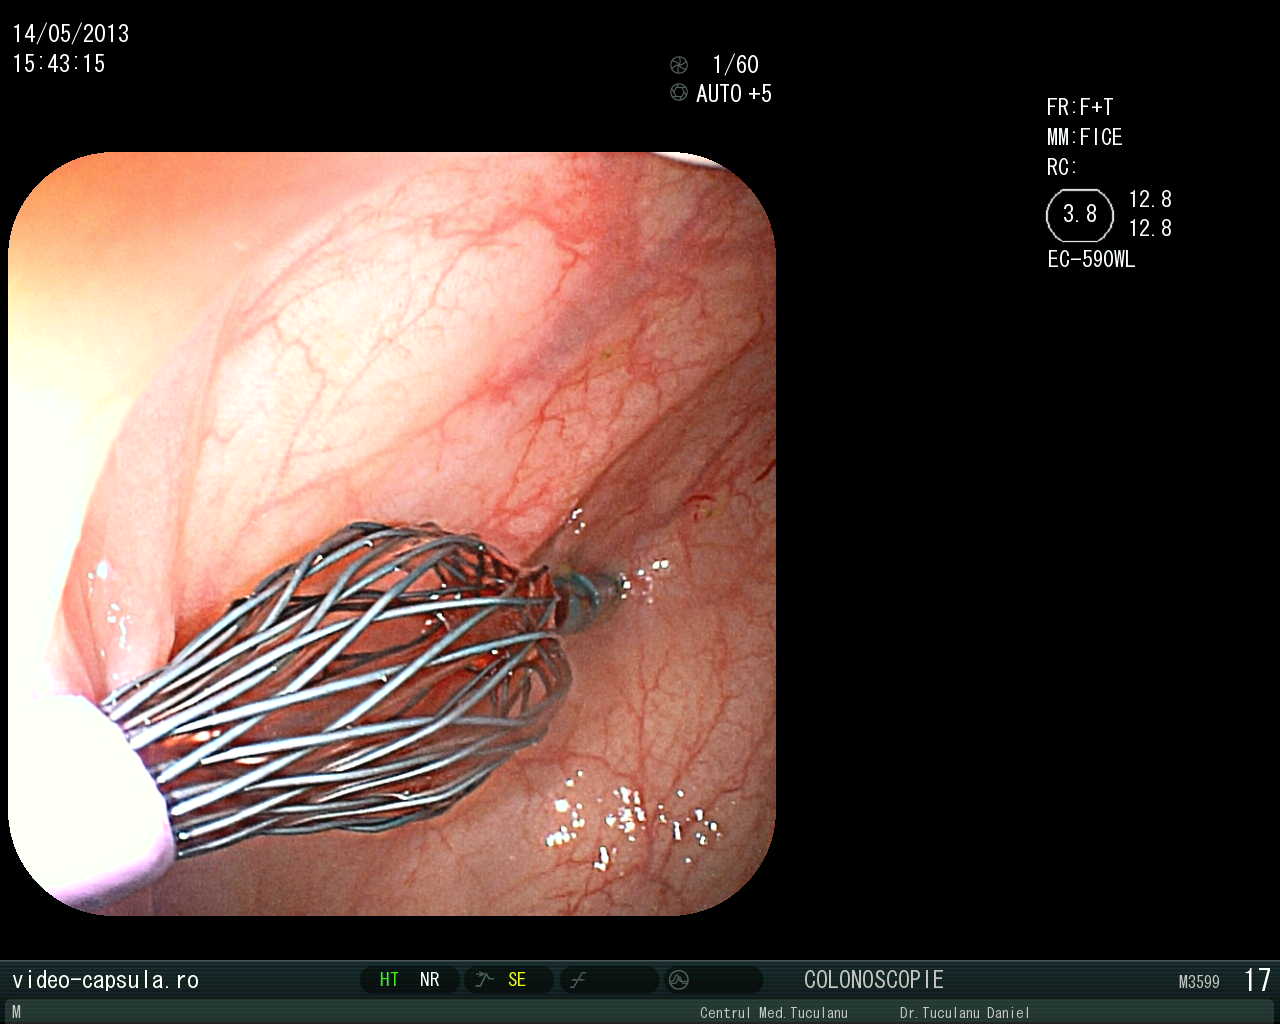

• Stent în cancer sigmoidian inoperabil •

Tratament endoscopic (nechirurgical) pentru evitarea operației paleative sau anusului contra naturii în cancerul colo-rectal avansat

Montarea de stent-uri (proteze) esofagiene, duodenale sau colo-rectale în stenoze canceroase sau necanceroase